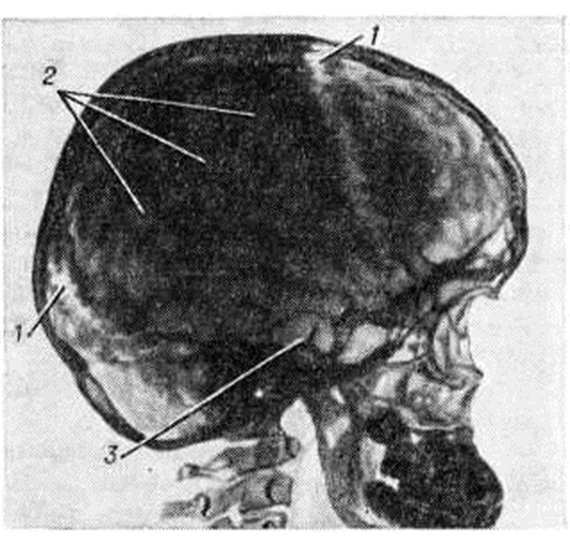

Анатомия детского черепа: Рентгеновские снимки и описание